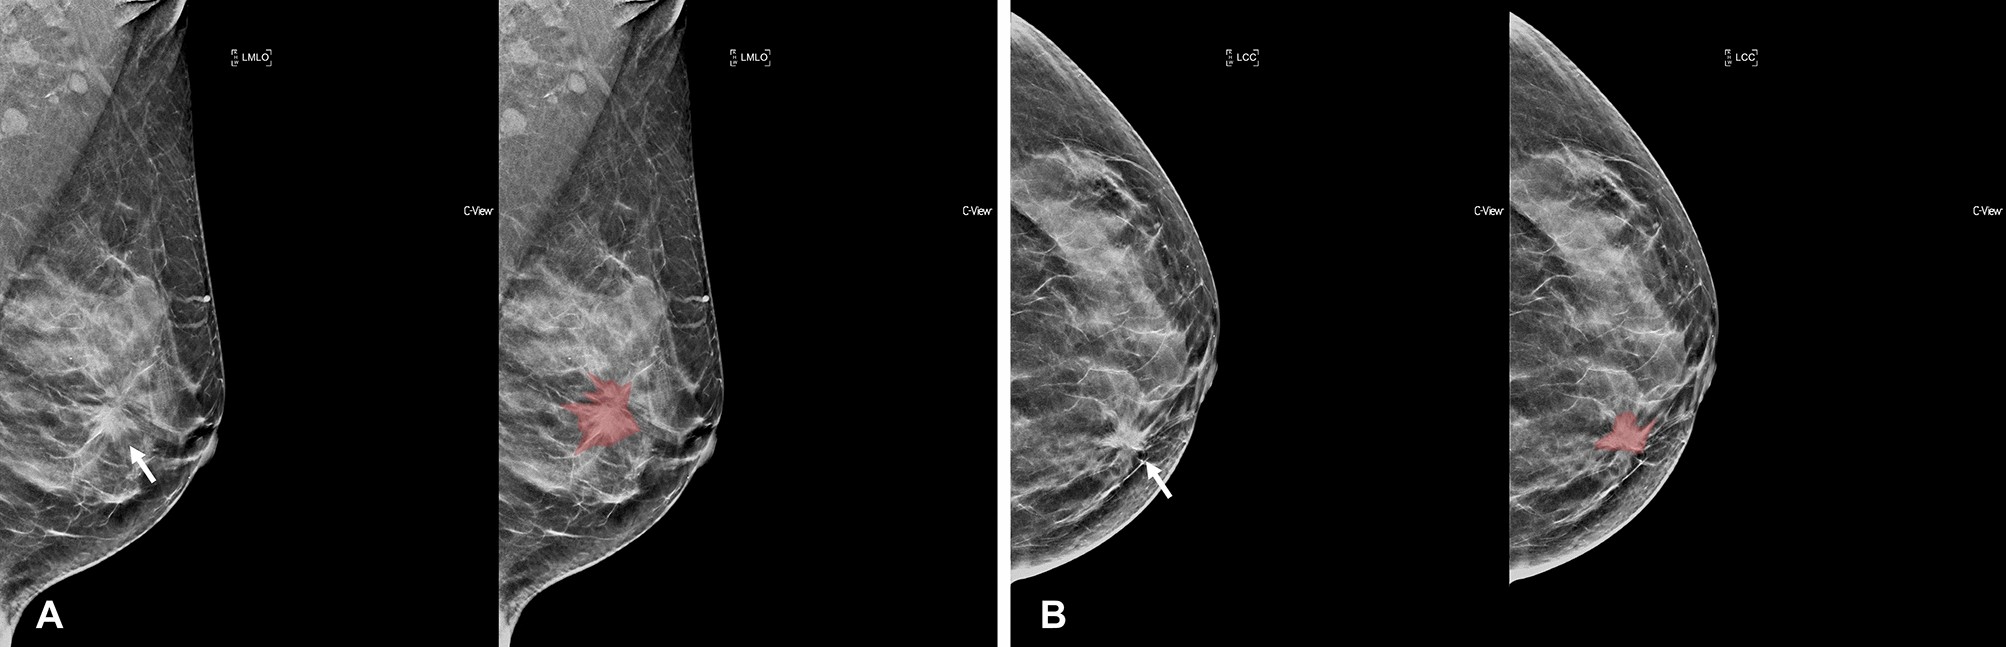

Figure 3

Segmentation example 2. Example of tumor segmentation on synthetic mammography. The synthetic mediolateral oblique (A) and craniocaudal (B) views of a 47-year-old female diagnosed with the luminal subtype of breast cancer. The breast lesion appears as a spiculated mass with architectural distortion (arrow).